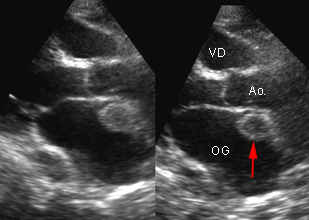

IRM cardiaque effectuée chez un patient de 48 ans en raison d’un aspect suspect de thrombus apical décelé en échographie dans les suites de plusieurs accidents emboliques systémiques : ilio-fémoral (désobstrué), mésentérique et rénal. Contexte d’EOA colique opéré et d’hépatectomie partielle pour métastases hépatiques. L’examen IRM retrouve un petit résidu thrombotique apical mobile (ciné), sans anomalie de la contraction segmentaire et révèle 2 foyers d’hypersignal pathologique post-gadolinium, enchassés dans l’épaisseur du myocarde, en inféro-latéral distal et en antéro-basal, en faveur de vraisemblables métastases cardiaques (flèches).